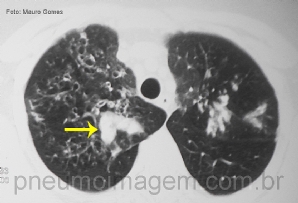

CASO CLÍNICO #20

O caso desse mês é uma imagem curiosa. O que a seta aponta? Deixe seus comentários abaixo. ***** The case of this month is a curious image. What the arrow points? Write your comment below.